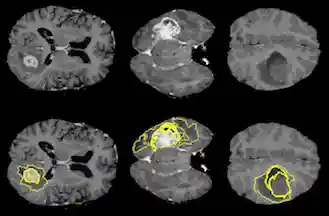

All MRI data was provided by the 2015 MICCAI BraTS Challenge, which consists of approximately 250 high-grade glioma cases and 50 low-grade cases. However, due to the limited time Each dataset contains four different MRI pulse sequences, each of which is comprised of 155 brain slices, for a total of 620 images per patient. Professional segmentation is provided as ground truth labels for each case. Figure 1 is an example of a scan with the ground truth segmentation. The segmentation labels are represented as follows:

Figure 1: Ground truth segmentation overlay on a T2 weighted scan.MRI Background

High-grade malignant brain tumors are generally associated with a short life expectancy and limited treatment options. The aggressive nature of this illness necessitates efficient diagnosis and treatment planning to improve quality of and extend patient life. This urgency reinforces thee need for reliable and fast automatic segmentation methods in clinical settings. Unfortunately, algorithmic segmentation of these particular tumors has proven to be a very challenging task, due primarily to the fact that they tend to be very structurally and spatially diverse (Figure 6).

Figure 6: Three different examples of high grade gliomas, tumor segmentations are outlined on the bottom images. Notice the variation in size, shape and location in the brain, a quality of these tumors that makes them difficult to segment.Convolutional Neural Networks